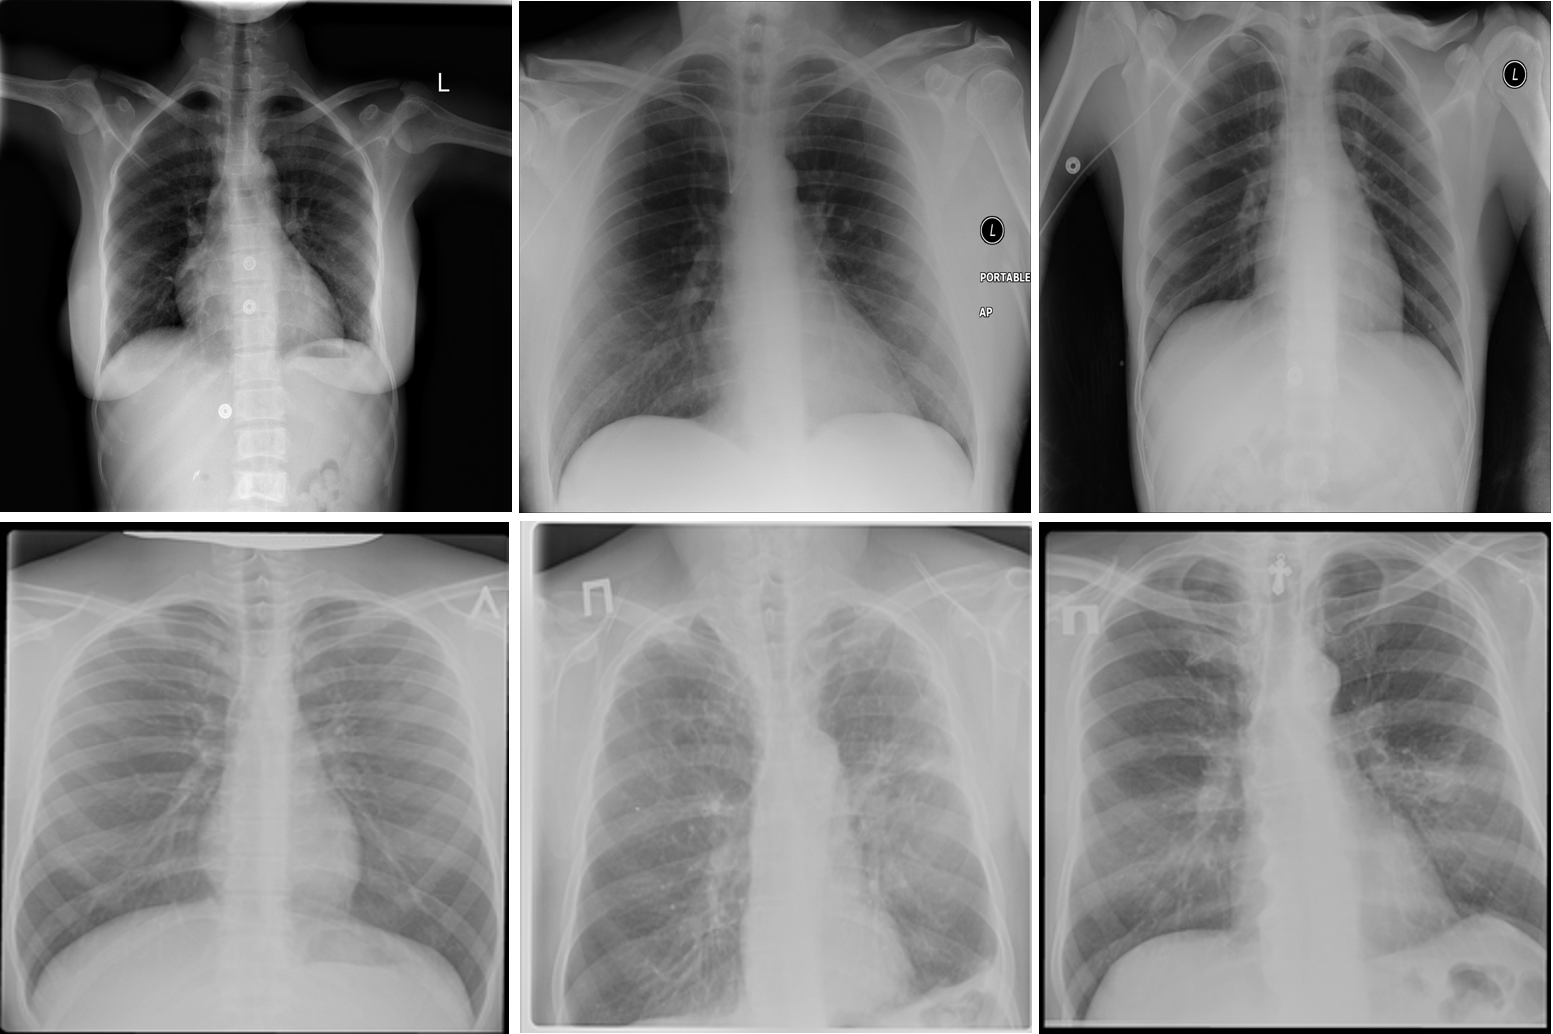

Refer to caption

Figure 1: Example chest X-ray images from the multi-national patient cohort introduced by Rahman et al. [15]: (top) TB negative patient cases and (bottom) TB positive patient cases.

After additional image quality screening of the CXR images, the CXR data used in this study comprises 6,939 CXR images. In terms of data distribution, there are a total of 3,461 CXR images from TB positive patients and 3,478 CXR images from TB negative patients. The training, validation, and test data consist of 80%, 10%, and 10% of the patient cases randomly selected from the multi-national patient cohort, respectively. To facilitate for the training and evaluation of TB-Net, the CXR images were resampled to 224×\times224 and mean imputation was performed on the top left-hand and top right-hand corners to mitigate the presence of embedded markings found in the CXR images. Example CXR images from the multi-national patient cohort used in this study for both TB negative and TB positive patient cases are shown in Figure 1.